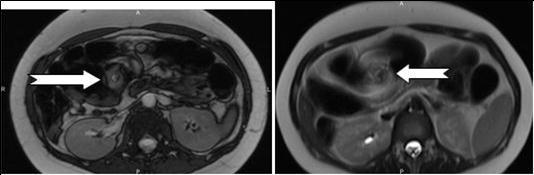

Figure 2A.Axial contrast-enhanced MRI scans show characteristic whirpool appearance of bowel and mesentery wrapping around superior mesenteric artery

Axial contrast-enhanced MRI scans show characteristic whirpool appearance of bowel and mesentery wrapping around superior mesenteric artery

A 28 weeks and 4 days pregnant, 29 years-old female, known for an L4-L5 discopathy and a past history of surgery for appendicitis at the age of 10 (right-positioned appendix, not perforated), consulted with vomiting and abdominal pain in the epigastric region. Eating and drinking had become impossible at that point. Blood tests revealed pathologically elevated white blood cells count (11.4 G/l for a normal value of 4-10 G/l) and elevated hepatic tests. Preeclampsia and HELLP syndrome were ruled out, as were frequent causes for hepatitis (virus, medicines, auto-immunity). Abdominal echography did not reveal any sign of cholecystitis or pancreatitis and testing for urinary cause was negative. The second blood tests revealed a worsening of the hepatic tests, reason why the patient underwent a cholangio-MRI. This test did not reveal any biliary lesion but volvulus was suspected due to apparent intestinal malrotation. Obtruction was confirmed by gastroscopy (without scope) and situated at the level of the jejunum. Final confirmation of obstruction and its position in the abdomen was also obtained through intestinal MRI (see Figure 2A, Figure 2B, Figure 3). During this time, the patient never displayed any gynaecological signs and foetal echography revealed a foetus with cephalic position, weighting 1300g and a posteriorly inserted healthy placenta with a Manning score of 10/10. The patient was referred for surgery. She underwent an exploratory laparoscopy that revealed multiple adhesions of the small intestine. Volvulus of the small intestine was identified just at the level of the duodeno-jejunal angle, situated on the right side of the aorta. Removal of the adhesions was attempted but ended up causing a small lesion of the small intestine, prompting the transformation of the laparoscopy into an open laparotomy. The laparotomy revealed a volvulus of the small intestine with common mesentery, with encircling of the caecum, the last part of the ileum and the beginning of the jejunum by the omentum. Resolution of the volvulus showed absence of intestinal rotation at the duodeno-jejunal angle, confirming the presence of malrotation. Mesentery was repositioned (without Ladd’s procedure) and fixation of the right colon to the right peritoneum was performed. The small intestine, which showed no sign of ischemia, was sutured and adhesions were completely removed. A few hours after the surgery, the patient presented with uterine contractions every two minutes and uterine ultrasonography showed a 33mm cervix. Tocolysis was immediately given with good results and the contractions definitely ceased and did not reappear two days later when treatment was stopped. During her stay, the patient presented with left basal pneumonia that was treated with antibiotherapy. She completely recovered during the following days and was then discharged with no further complication. The rest of her pregnancy went without any other complication and the patient delivered with instrumentation (Kiwi-sucker) at the age of 40 weeks and 0 days due to a suspect cardio-tocogramm and absence of delivery progression. Both baby and mother were healthy and they were then discharged with no further complication

In that aspect, small bowel volvulus should always remain in the differential diagnosis in front of a pregnant woman presenting with abdominal pain during pregnancy, especially one like ours that was known for a previous surgery for appendicitis (a possible reason for the presence of the adhesions). Radiologic diagnosis of small bowel volvulus can be done by several technics. Plain abdominal film can be used, showing sometimes a typical pattern of dilated loops, but more often showing a normal radiological pattern due to a proximal position of the volvulus (with the loops being filled with liquid). Evidences on CT-scan are the presence of dilated bowel loops, intramural gas and the “whirlpool sign” (Cong et al, 2014; Shui et al, 2011)4, 12, but the use of technics exposing the foetus to radiations is debated. However, in their review, Cong et al 4emphasized the fact that those technics (and particularly plain radiography) are considered safe for the mother as well as for the foetus (Cong et al, 2014)4. MRI is also safe and extremely precise in the diagnosis of small bowel obstruction (Vassiliou et al, 2012)13, sometimes also showing the “whirlpool sign” (Kouki et al, 2013)7 and ultrasonography has been reported to be useful in some instances (Cong et al, 2014)4 but it can also remain completely negative. In our case, while cholangio-MRI suggested the diagnosis, final diagnosis was given by intestinal MRI, showing a possible role for this technic in some unusual cases, in which doubts about the diagnosis or about the state of different abdominal structures remain. However, in cases in which clinical symptoms, laboratory and more basic radiological (plain abdominal film of CT-scan) are highly suggestive of this pathology, exploratory surgery should be started at the earliest time possible.